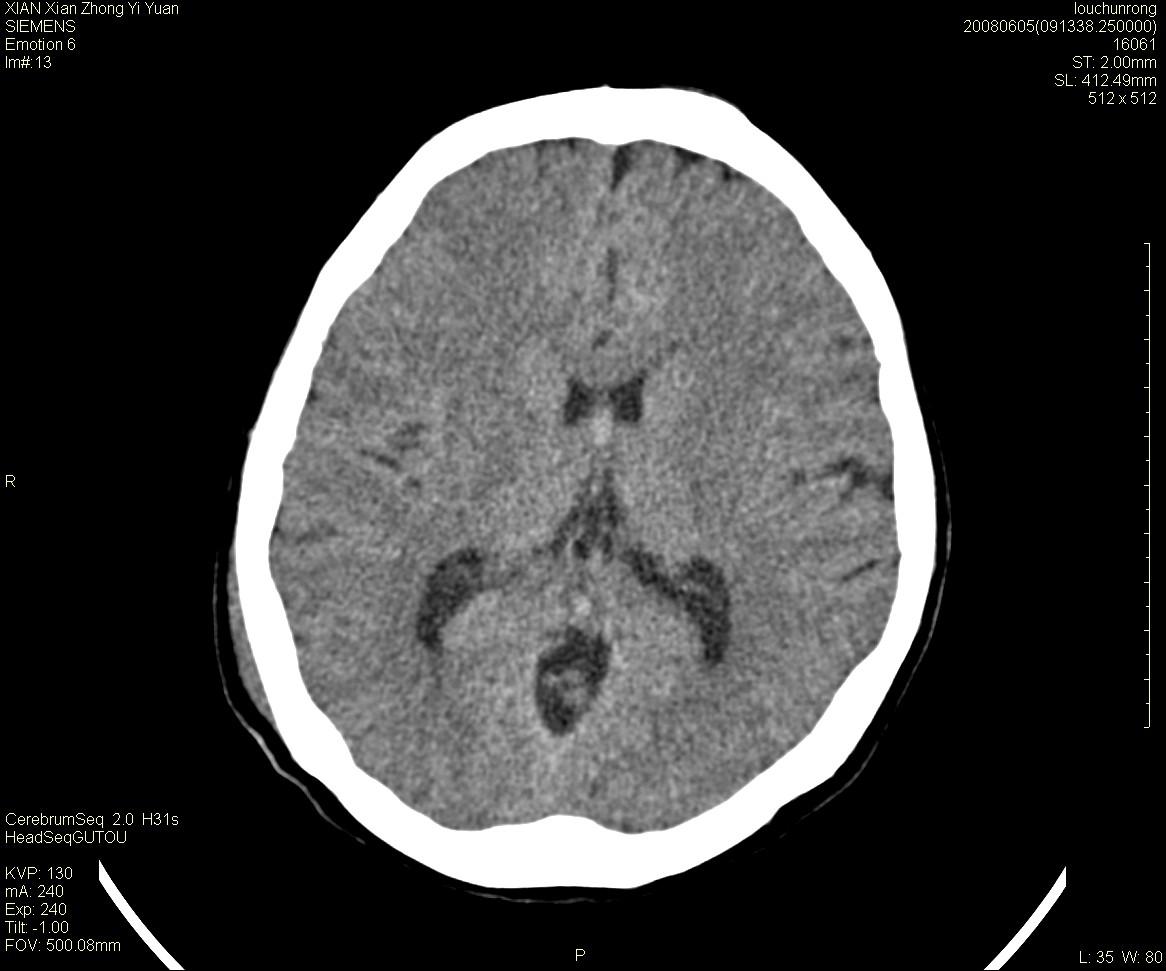

标题: CT13860:F52Y,,头外伤致头晕半天,以前无不适。 [打印本页]

标题: CT13860:F52Y,,头外伤致头晕半天,以前无不适。

层厚2mm。

左侧侧室内血管异常增粗,考虑血管变异或血管瘤可能,余未见异常

两侧脑室体部距离增宽,胼胝体发育不良?

中线附近、枕叶近枕骨处及脑内多发点条状强化影,考虑血管异常?

侧脑室前角变形、变窄,考虑侧脑室粘合;余未见明显异常。